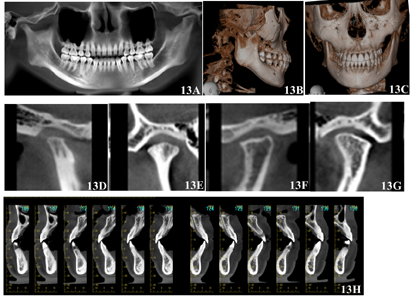

该患者矫治时间共29个月,矫治后患者自然状态下左右面部基本对称,颏部无明显偏斜,面下1/3高度减小,相貌趋向直面型,颏部肌肉放松。口内检查显示,前牙达到正常覆合覆盖,双侧尖磨牙I类咬合关系,上下中线齐,上下牙弓均呈光滑卵圆形,患者具有前牙和尖牙保护合。曲面断层X线片显示矫治后各牙牙根平行度尚可,未见明显牙根及牙槽骨吸收。CBCT显示左侧关节间隙减小,双侧髁突骨皮质连续;各牙根尖均位于松质骨内。矫治后头颅侧位X线片显示:SNA角80.5°,SNB角78.6°,ANB角1.9°,FH-MP角35.0°,PP-GoGn角29.4°,矫治后FH-MP角较术前减小1.9°。矫治前后头颅侧位片X线片重叠图显示下颌稍有逆时针旋转。术后2年随访记录显示患者面部无明显偏斜,咬合关系良好,双侧髁突骨皮质连续光滑,牙齿根骨关系正常,治疗效果稳定(图9,图10,图11,图12,图13,表1)。